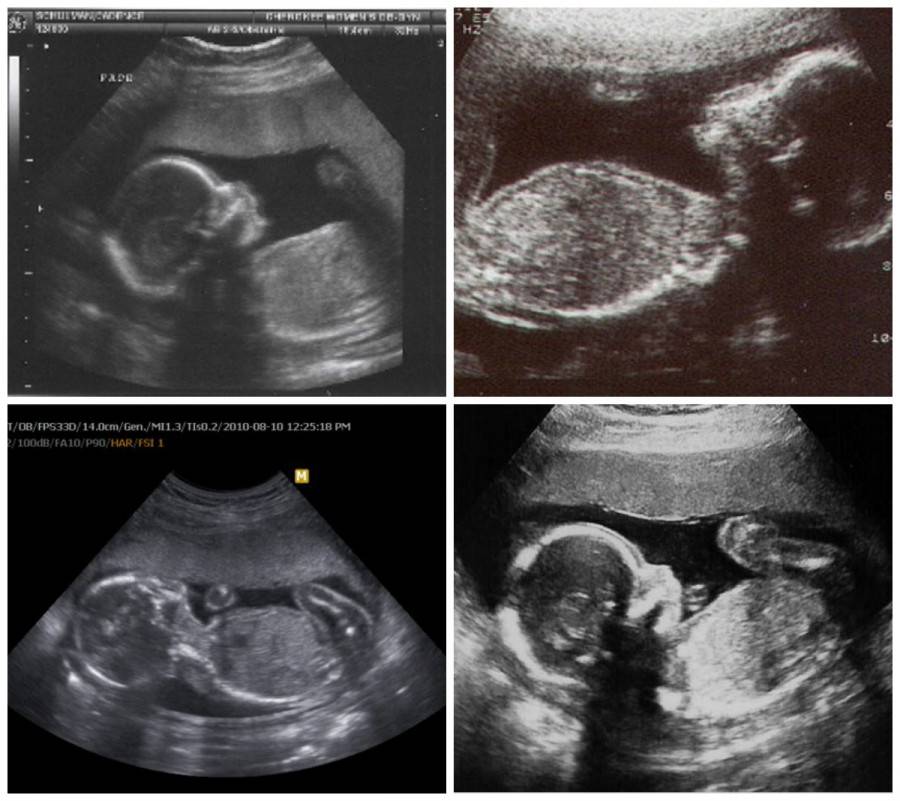

УЗИ на 21 неделе беременности

Во время ультразвукового исследования на 21 неделе беременности можно рассмотреть все части тела будущего ребенка, полушария его головного мозга, сердце, крохотные косточки, позвоночник, внутренние органы. Можно увидеть движения и определить пол плода. Многие будущие родители с нетерпением ждут этого момента и очень расстраиваются, если малыш загораживает половые органы от датчика. Но некоторые женщины хотят, чтобы это был сюрприз, и специально просят врача не говорить пол ребенка.

Некоторые будущие мамы и папы поступают еще более креативно. Они просят врача распечатать снимок, написать на нем пол плода, но не сообщать его, а убрать в конверт. Уже после рождения малыша конверт вскрывают. Многие признаются, что это очень захватывающий и волнительный момент.

Доплерометрия помогает оценить кровоток в сосудах плода и плаценты, проверить состояние сердца. Во время исследования можно услышать звуки сердцебиения будущего ребенка.

Картина во время УЗИ на 21 неделе беременности выглядит следующим образом: